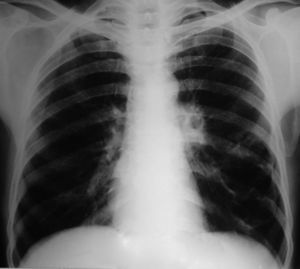

Caso clínicoUn hombre de 45 años de edad solicitó una valoración de su médico de cabecera tras los antecedentes de esputo hemoptoico y tos seca de un mes de duración. Por consiguiente, fue derivado al hospital de los autores después de que la visión posteroanterior de una radiografía de tórax (fig. 1) mostrara la presencia de un quiste en el lóbulo inferior izquierdo (LII). En la valoración inicial se obtuvo una anamnesis en la que el paciente refirió antecedentes de tabaquismo de 26 paquetes/año. También refirió que en la radiografía de tórax previa, efectuada 2 años antes en una revisión médica anual sistemática, no se encontraron anomalías. Tampoco tenía antecedentes de enfermedades respiratorias previas. La exploración física reveló una disminución de la intensidad del murmullo vesicular sobre las áreas inter e infraescapulares internas. La tomografía computarizada (TC) de tórax reveló un quiste de forma irregular y pared fina, junto con una disminución generalizada de la atenuación en el LII (fig. 2). Se programó una broncoscopia de fibra óptica (BFO), pero el paciente se perdió para el seguimiento. Más tarde regresó tras un período de 2 meses, en vista de los síntomas crecientes. Se asociaban con anorexia y una pérdida de peso de 4kg. La TC repetida de tórax (fig. 3) demostró el colapso completo del LII que contenía un quiste lleno de líquido, colapsado (flecha negra). También se observó una masa en la región hiliar izquierda con la pérdida de los planos de grasa en la aorta descendente. En la BFO (vídeo 1) se observó una proliferación en el bronquio principal izquierdo a 4cm de la carina que ocluía por completo el bronquio principal del LII. En la biopsia endobronquial se demostró la presencia de un carcinoma de células escamosas (fig. 4). Más tarde, el paciente recibió 4 ciclos de quimioterapia con docetaxel y cisplatino, seguidos de radioterapia torácica (secuencial) como tratamiento combinado para un cáncer de pulmón no microcítico en estadio IIIB. Más adelante se demostró la progresión de la enfermedad, y falleció alrededor de 10 meses después del diagnóstico.